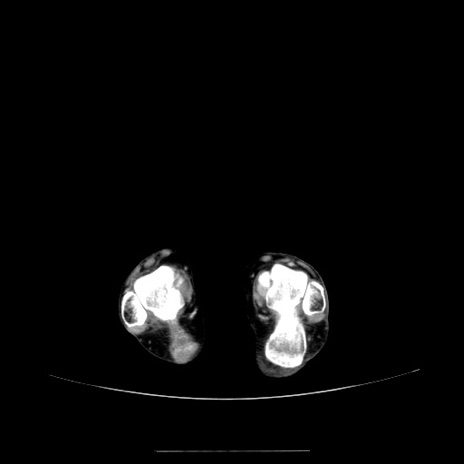

症例5(横断像)

【症例】70歳代女性

【主訴】お腹が張る

【現病歴】1週間くらい前から腹部膨満の自覚あり。昨日夜から増悪したため、本日救急外来受診。

【身体所見】意識清明、BT 36.5℃、BP 165/106mmHg、HR 80bpm、SpO2 98%、腹部:膨満、軟、自発痛・圧痛なし、触診にて不快感あり、腸蠕動音:減弱

【データ】WBC 12600、CRP 1.04